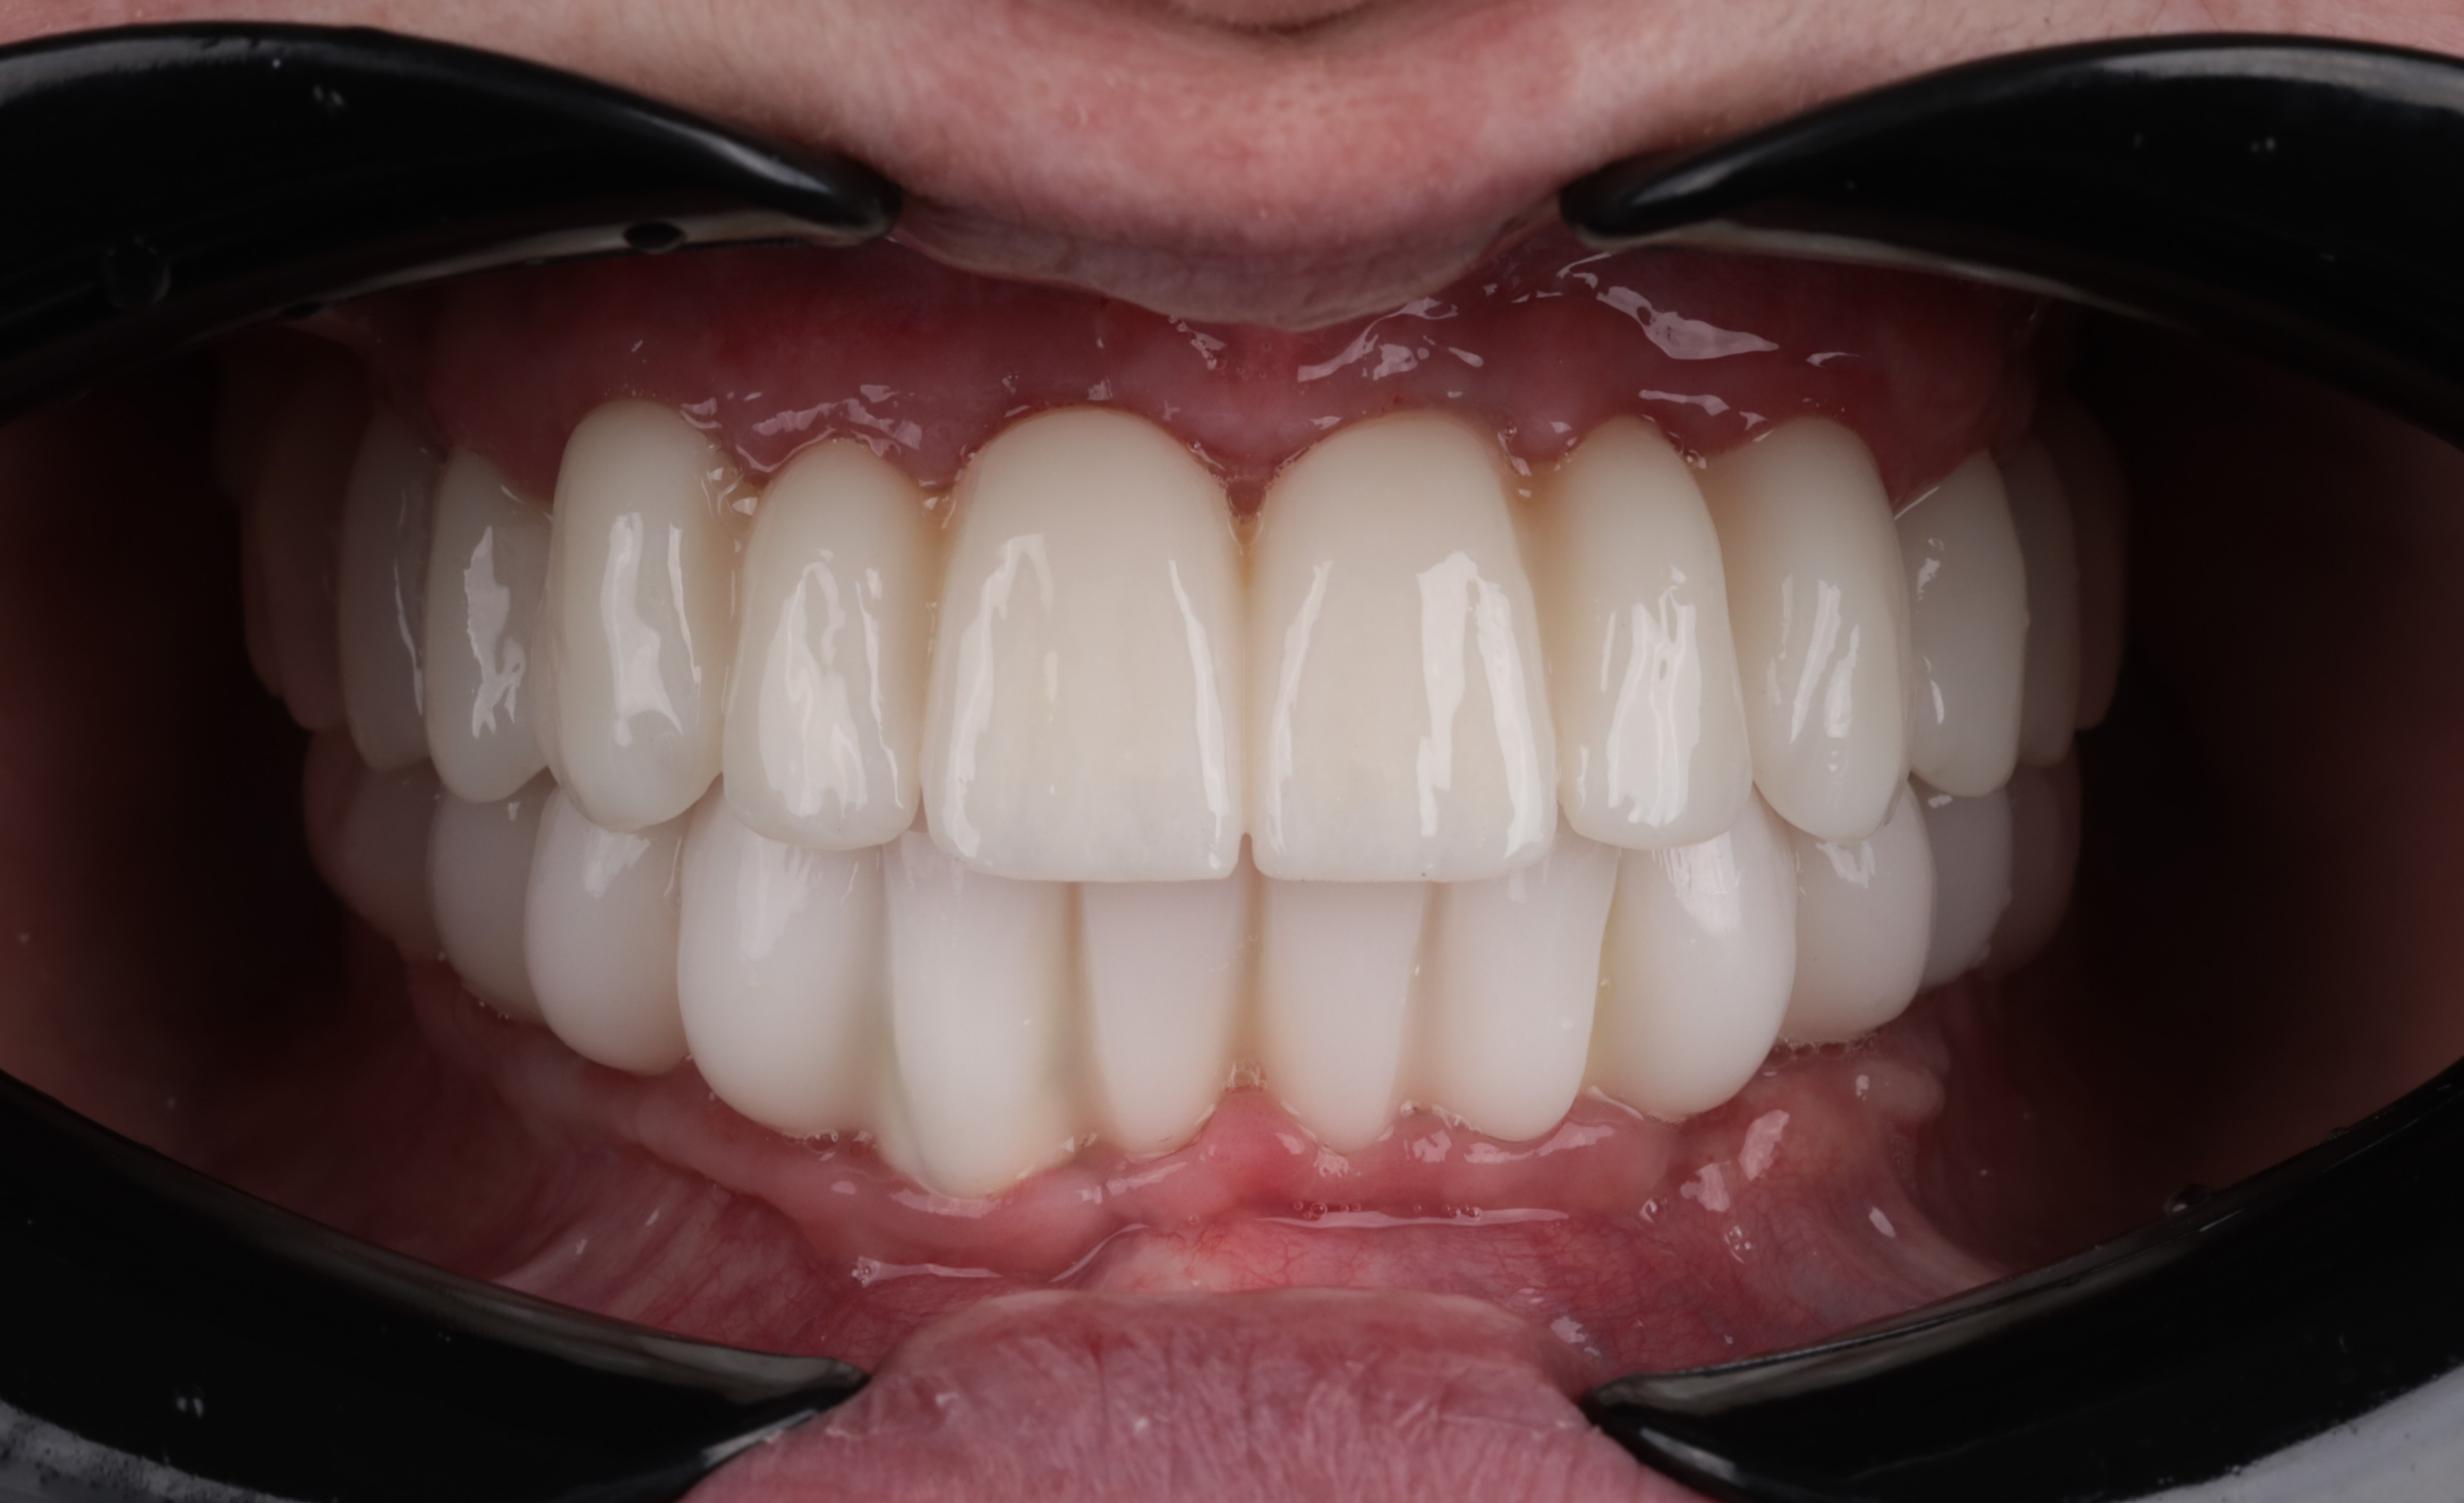

The final restorative phase utilized a repeat IPG scan to ensure micron-level accuracy for the definitive frameworks. The maxilla was restored with a zirconia bridge on a titanium framework, while a metal-composite framework was selected for the mandible. The definitive prostheses achieved a perfect passive fit and optimal seating, successfully restoring both masticatory function and the patient’s natural aesthetic smile.